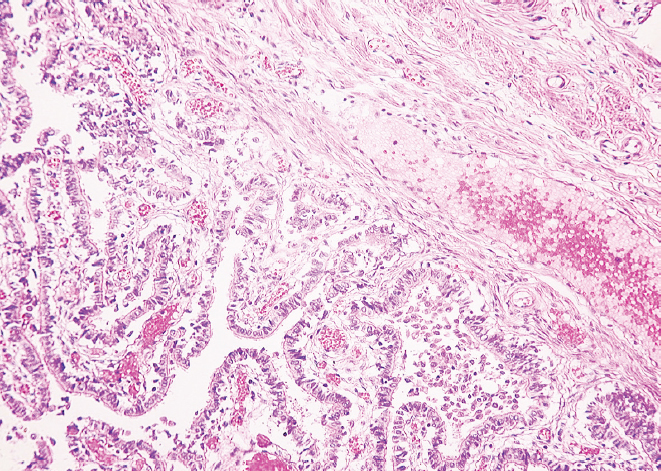

RESULTS: There was a decrease in the external diameter of the isthmus and funnel of both fallopian tubes in women from young age to old age (p < 0.01). At old age, there was a predominance of external diameter parameters of the isthmus and funnel of the right fallopian tube in comparison with those of the left fallopian tube (p < 0.01), while at young age there was only a tendency for the diameter of the isthmus and funnel of the right fallopian tube to predominate (p > 0.05). The histological study showed the presence of thickened folds of the mucous membrane and flattened epithelium in the studied areas in older women, thinning of the muscular membrane layers and overgrowth of connective tissue in comparison with the samples taken for the study in younger women.

CONCLUSIONS: Morphologic restructuring of the isthmus and funnel of the fallopian tubes from young to old age consists in thickening of the mucous membrane folds, flattening of the epithelium, overgrowth of connective tissue in the wall and reduction of their outer diameter with predominant parameters in the right fallopian tube.